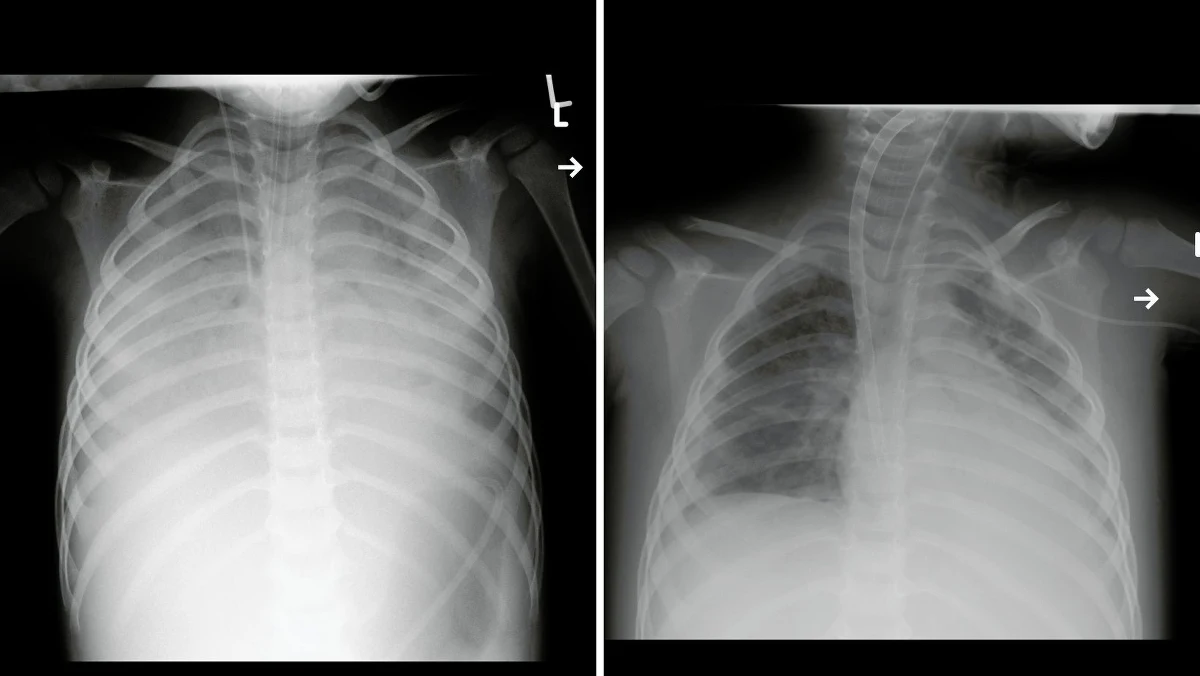

Jeden z ostatnich pacjentów, który pojawił się tu z takim powikłaniem, praktycznie rzecz biorąc, stracił płuca. Musiał być podłączony do bardzo wysokospecjalistycznej aparatury, który za niego oddychała (to było urządzenie ECMO, sztuczne płuco-serce, które przepompowuje krew i poza organizmem jest ona natleniana, a potem znów wprowadzana do krwiobiegu pacjenta - przyp. red.). Fachowość lekarzy, którzy się zajmowali chorym, spowodowała, że odzyskaliśmy tego pacjenta. Jego płuca można zobaczyć na zdjęciach, które zrobiliśmy w chwili przyjęcia do szpitala i później po kilkunastu dniach stosowania ECMO - podkreśla prof. Zeman.